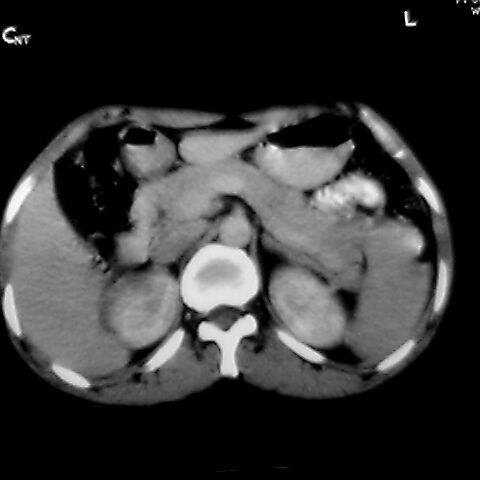

女 48岁 食道癌术前体检发现脾占位。

脾胀内部巨大低密度肿块,边界清或不清,中心坏死,轻度增强,内见散在钙化,结合食道癌病史多考虑:转移癌.

考虑脾脏血管瘤,中央低密度为血栓形成

脾脏低密度灶伴钙化,增强化明显,中心见液化坏死灶,强化延时明显。考虑血管瘤。转移瘤待排。

转移瘤不可能单发,考虑脾血管瘤。